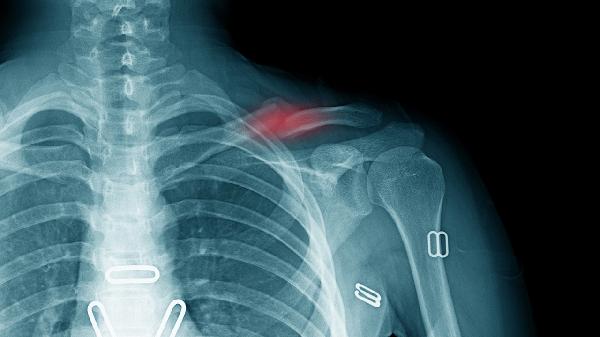

锁骨骨折吃什么补品

锁骨骨折恢复期需保持均衡饮食,多摄入富含钙质的乳制品、深绿色蔬菜及海产品,配合适度阳光照射。避免吸烟饮酒及高盐饮食,定期复查X线观察愈合进度。如出现局部红肿热痛或异常活动,应及时就医评估。